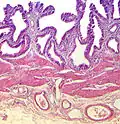

Hematoxilina

La hematoxilina es un colorante nuclear. Hay variedad de ellas siempre usando la base de hematoxilina extraída del árbol palo campeche. Existe la hematoxilina de Mayer, de Harris, y otras. Utilizado con un mordiente, la hematoxilina tiñe los núcleos celulares de color azul violeta a negro. Con gran frecuencia se utiliza en combinación con eosina en la coloración H&E (hematoxilina y eosina), una de las más comunes utilizadas en histología.

Eosina

La eosina se utiliza más frecuentemente como contracoloración de la hematoxilina, impartiendo un color que va del rosado al rojo al material citoplasmático, membrana celular, y algunas estructuras extracelulares. Además imparte un fuerte color rojo a los eritrocitos. La eosina puede ser utilizada también en algunas variantes de la coloración de Gram, y en muchos otros protocolos de tinción. De hecho existen dos compuestos muy estrechamente relacionados (aunque no iguales) conocidos como eosina. El más frecuentemente utilizado es la eosina Y (también conocida como eosina amarillenta) ya que posee una tonalidad amarillenta muy suave. El otro compuesto conocido como eosina es la eosina B, también conocida como eosina azulada o rojo imperial, la cual posee una suave tonalidad azul. Los dos colorantes son intercambiables, y el la utilización de uno u otro es más una cuestión de preferencia y tradición.